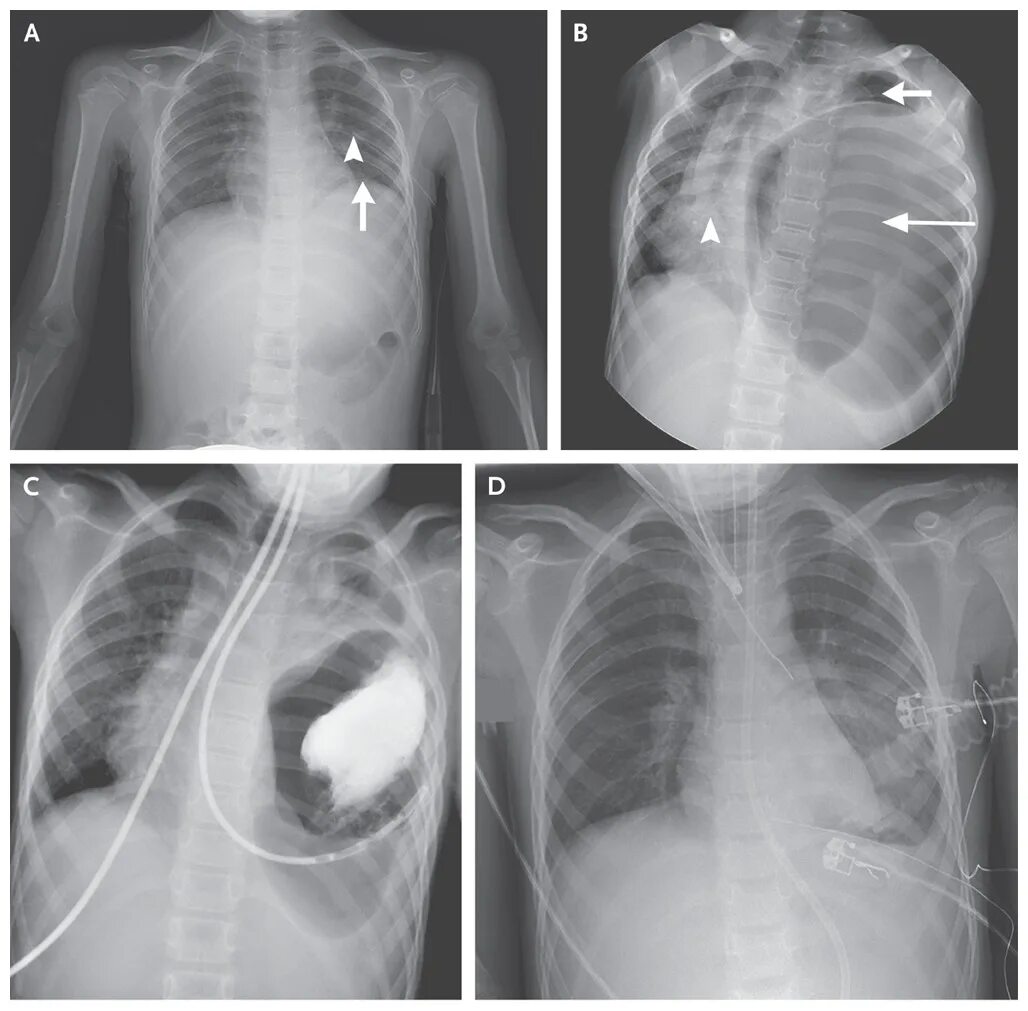

Грыжа рвота